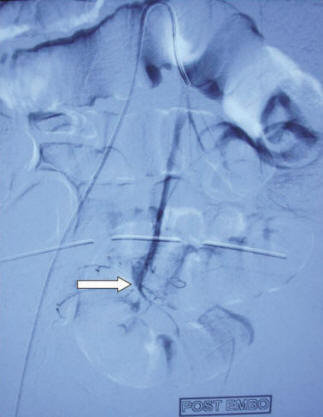

embolization Of A Gi Bleed - Endovascular Today

Embolization of a Gi Bleed (approximately 2:00 AM) with rectal bleeding. When she arrived to the hospital, she was hemody-namically stable but had further rectal bleeding. After Embolization is a quick and effective treatment for lower GI bleeding.n ... Read Here